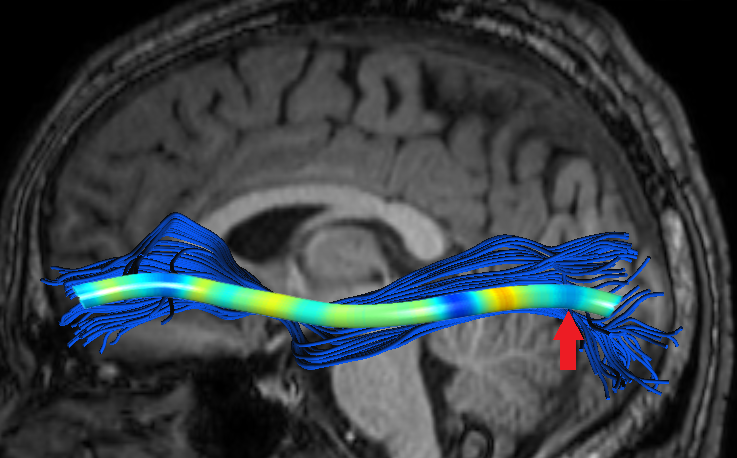

Experiments also showed significant FFDD longitudinal changes between mid-season and post-season scans in some football players. Fig. 7 presents mid- and post-season MD-FFDD profiles comparison of the left IFOF of one of the players, showing increased irregularities over time at the occipital part of the tract. Fig. 8 presents a similar MD-FFDD longitudinal analysis of the FMT of a different player, showing increased irregularities at the central part of the tract.

| Mid vs. Post | Mid-season | Post-season | ||

|---|---|---|---|---|

![]() |

|

STDs |